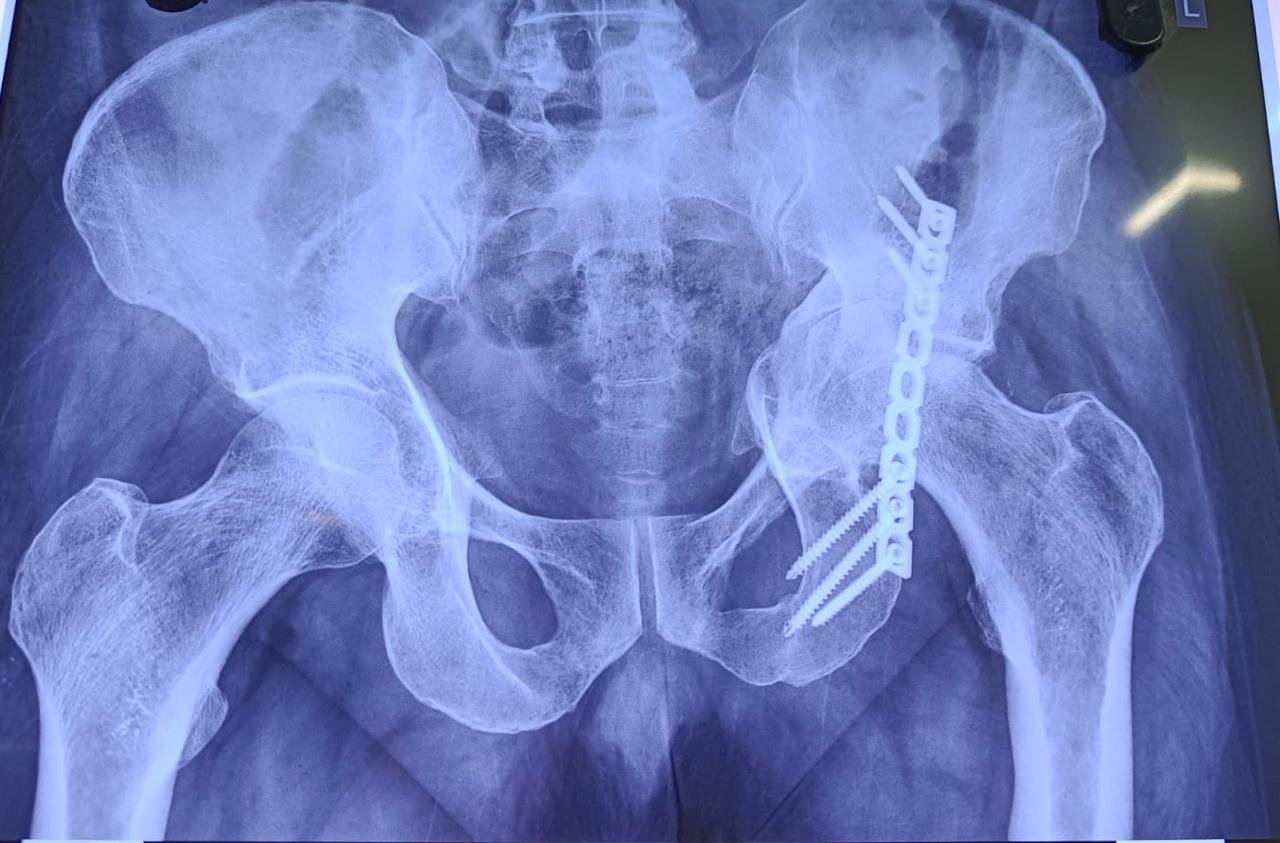

AVN with Protrusio following Acetabular Fixation

Pre-Op X-Ray

Non Union & Fixation Failure Post CHS